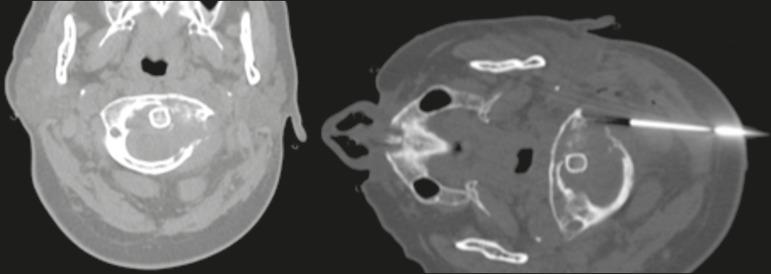

We evaluated 74 biopsies performed in 68 patients. The mean age of the patients was 55.6 years. Most of the lesions (79.7%) were located in the suprahyoid region, and the maximum diameter ranged from 11 mm to 128 mm. The most common approaches were paramaxillary (in 32.4%), retromandibular (in 21.6%), and periorbital (in 14.9%). Five patients (6.8%) developed minor complications. The presence of a complication did not show a statistically significant association with any clinical, radiological, or procedure-related factor. Sufficient material for histological analysis was obtained in all procedures. Thirty-eight biopsies (51.4%) yielded a histological diagnosis of malignancy. There was a false-negative result in three cases (8.3%), and there were no false-positive results. The procedure had a sensitivity of 92.7%, a specificity of 100%, and an accuracy of 96.0%.

我们评估了68例患者的74次活检。患者的平均年龄为55.6岁。大多数病变(79.7%)位于舌骨上区,最大直径范围为11毫米至128毫米。最常见的进针途径是上颌旁(32.4%)、下颌后(21.6%)和眶周(14.9%)。5例患者(6.8%)出现轻微并发症。并发症的发生与任何临床、放射学或操作相关因素均无统计学显著关联。所有操作均获得了足够的组织学分析材料。38次活检(51.4%)组织学诊断为恶性肿瘤。3例出现假阴性结果(8.3%),无假阳性结果。该操作的敏感性为92.7%,特异性为100%,准确性为96.0%。